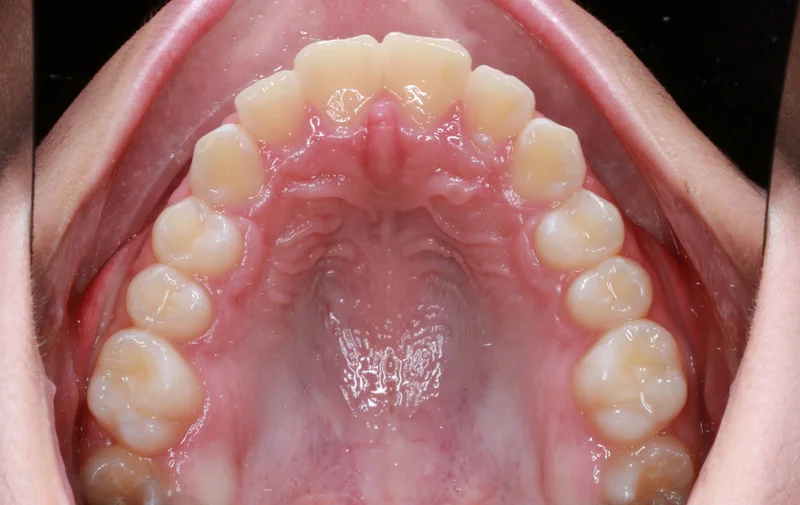

Upper Occlusal View

Upper Occlusal View - After Treatment

After